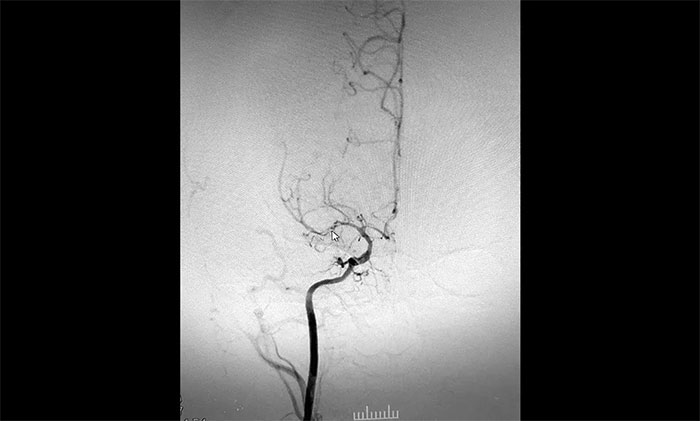

入院后,赵先生的DSA(脑血管造影)检查再次明确“烟雾病”表现:双侧大脑中动脉主干管腔纤细、分支细小;周围代偿性小血管网建立;右侧颈内动脉C3-4段纤细,显影毛糙;两侧颈内动脉C4-6段钙化形成伴管腔轻—中度狭窄。

▲DSA异常血管造影图

神经外科团队综合DSA检查结果和患者症状表现,进行了科学、审慎的评估。于耀宇主任谈到,患者双侧颈内动脉虹吸部和大脑中、前动脉主干近段明显狭窄、近乎闭塞,异常血管网形成。双侧大脑半球多发供血区灌注不足,尤以右侧缺血较为明显。